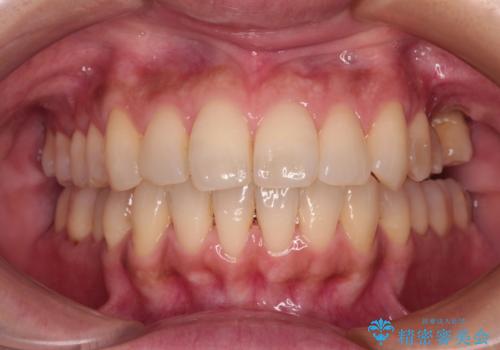

インビザラインによる矯正治療と奥歯のインプラント治療

- 全体的なデコボコと、以前抜歯した歯のスペースを閉じた部分が気になるとのことで来院された患者様です。

左上第一大臼歯を抜歯した際に、スペースを閉じたそうですが、歯が傾斜してものが挟まって不快とのことでした。

インビザライン矯正で全体の歯列と整えるとともに、左上第一大臼歯部にはスペースを作り、インプラントによる補綴治療を行うこととしました。

歯の傾斜が改善され、インプラントによるクラウンが装着されたことで、物が挟まることもなくなりました。